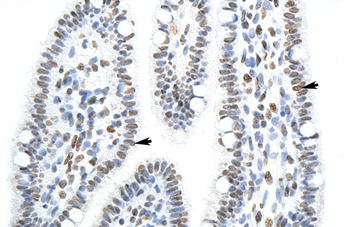

IHC analysis of SFPQ using anti-SFPQ antibody. SFPQ was detected in a paraffin-embedded section of human squamous cell carcinoma of the penis tissue. Heat mediated antigen retrieval was performed in EDTA buffer (pH8.0, epitope retrieval solution). The tissue section was blocked with 10% goat serum. The tissue section was then incubated with 2 µg/ml rabbit anti-SFPQ Antibody overnight at 4°C. Peroxidase Conjugated Goat Anti-rabbit IgG was used as secondary antibody and incubated for 30 minutes at 37°C. The tissue section was developed using HRP Conjugated Rabbit IgG Super Vision Assay Kit with DAB as the chromogen.